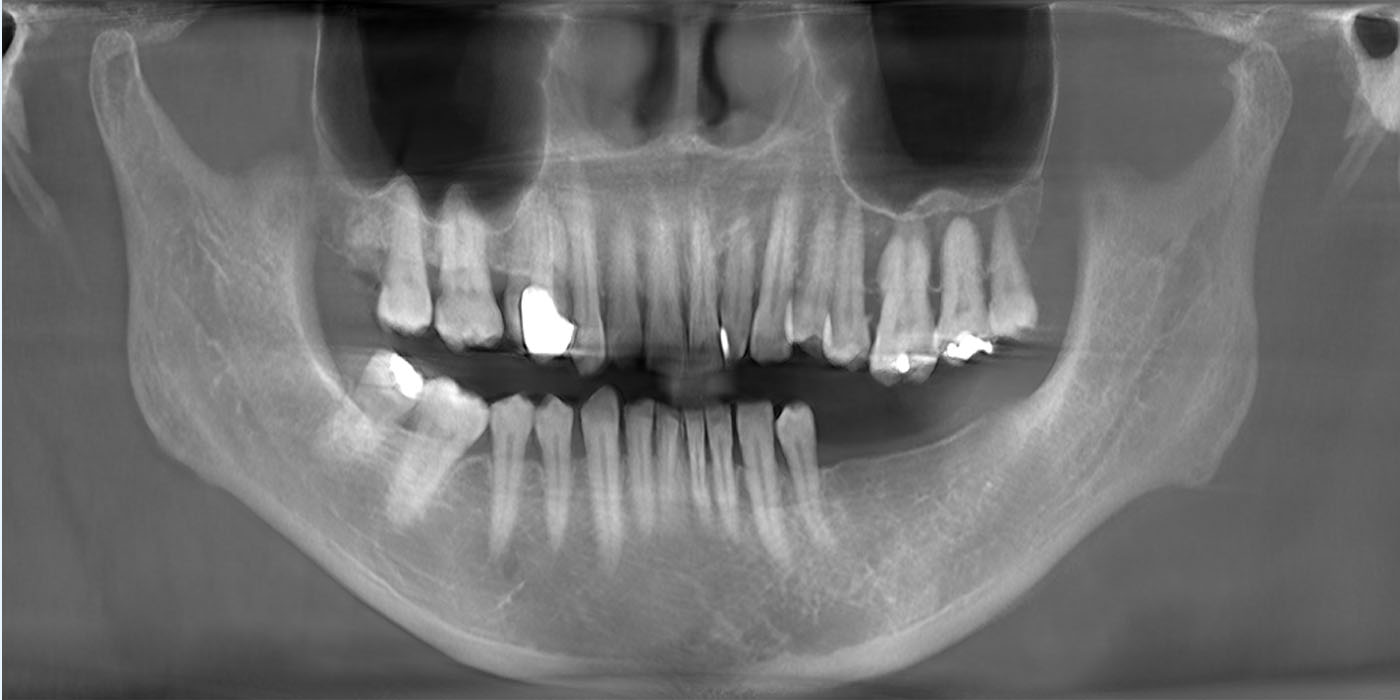

A panoramic radiograph is a panoramic scanning dental X-ray of the upper and lower jaw. It shows a two-dimensional view of a half-circle from ear to ear.

Panoramic radiography is a form of focal plane tomography; thus, images of multiple planes are taken to make up the composite panoramic image, where the maxilla and mandible are in the focal trough and the structures that are superficial and deep to the trough are blurred.